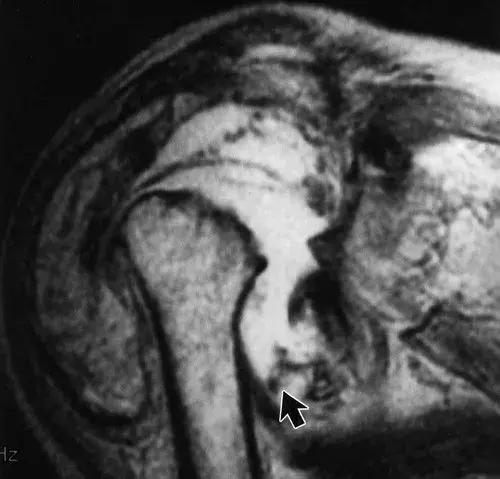

图3:患者28岁,T8截瘫,肩部神经性骨关节病。 (a)胸部X线片显示左盂肱关节实质性破坏(实线箭头)。 注意脊柱固定硬件(空心箭头)。 (b)轴向CT扫描显示由低衰减液体扩张的关节内衬的骨质碎片(箭头)。 (c)颈椎的T2加权自旋回波MR图像(2,400 / 80)显示广泛的空洞。